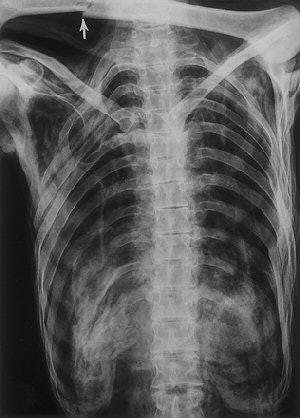

![]() |

| Irregular opacity (arrows) in the left shoulder retrospectively detected on a conventional frontal radiograph of the chest (obtained on September 26, 1991) has the general configuration of an arrowhead. Also in retrospect, the arrowhead is visible on the radiograph obtained on May 25, 1993 (top). Fig. 8, 21, Murphy WA, zur Nedden D, Gostner P, et al. "The Iceman: Discovery and Imaging," Radiology 2003; 226:614-629. |